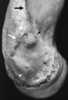

Supracondylar spur of humerus

The supracondylar process of the humerus (also known as an avian spur) is a variant bony projection on the anteromedial aspect of the upper arm bone (humerus), about 5-6 cm above the medial epicondyle. It is directed downward, forward and medially pointing to the medial epicondyle. [Source: Wikipedia ]